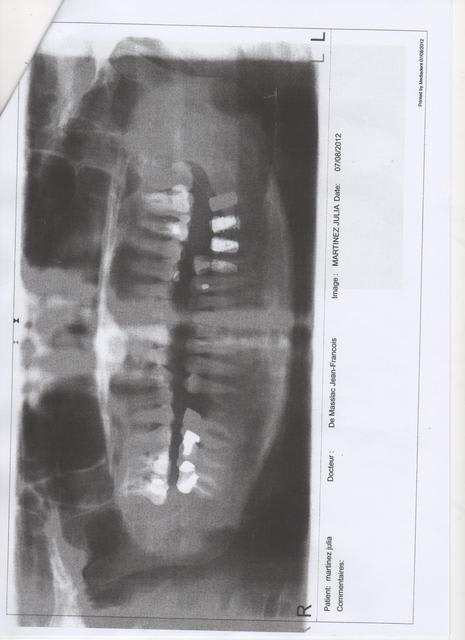

Quelqu un aurait il une idee sur ce genre d implants?

Poseur disparu et dossiers chez huissier ou détruits.

(peut etre made USA.. d apres patiente)

on t'avais demandé une radio...ok on a une pano...mais c'est illisible sur nonol, et en plus la qualité à l'air nulle...

donc, tu nous fais une jolie petite rétro nous montrant l'intégralité de "l'anatomie" de ces implants, de la connexion à l'apex et je pourrai t'aider...;-)

P.S: faut penser à retirer tout identification des images....on voit les noms sur ta pano...